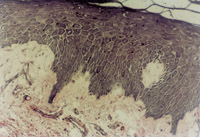

原位切取創(chuàng)面組織病理切片檢查,見壞死上皮組織間有大量顆粒樣組織,新生上皮細(xì)胞和膠原纖維組織呈團(tuán)樣增生,并可見到典型的類似于胎兒皮膚結(jié)構(gòu)的皮膚胚胎基(embryonic base,EB)(圖5-3-4a,5-3-4b)。MEBT治療10天后,在創(chuàng)面邊緣取上皮組織病理切片可見到較原始的上皮組織。

5-3-4a 新生上皮組織和膠原纖維增生,可見典型EB(皮膚胚胎基) HE×40

5-3-4b 新生上皮組織中可見微血管,膠原纖維和上皮細(xì)胞(干細(xì)胞)形成的皮膚胚胎基組織  HE×40